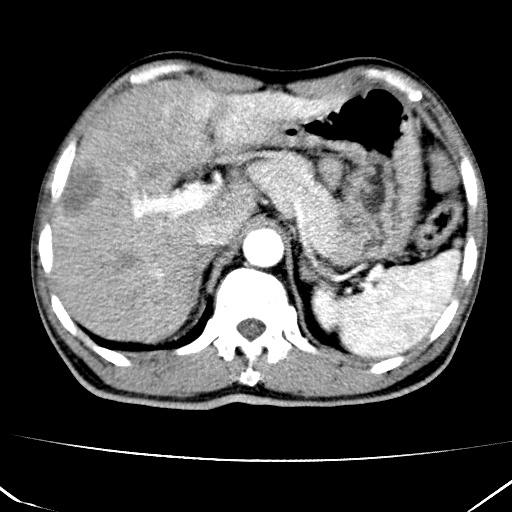

标题: CT17975:请求会诊。男、57岁。上腹部胀痛2天。临床诊断:糜 [打印本页]

标题: CT17975:请求会诊。男、57岁。上腹部胀痛2天。临床诊断:糜

肝脏多发类圆形低密度影,考虑肝脏转移瘤,肝胃韧带一淋巴结肿大,原发?胃癌?

考虑胃癌并肝脏及腹膜后淋巴结转移;不排除淋巴瘤。

肝内转移瘤,腹腔及腹膜后淋巴结转移。